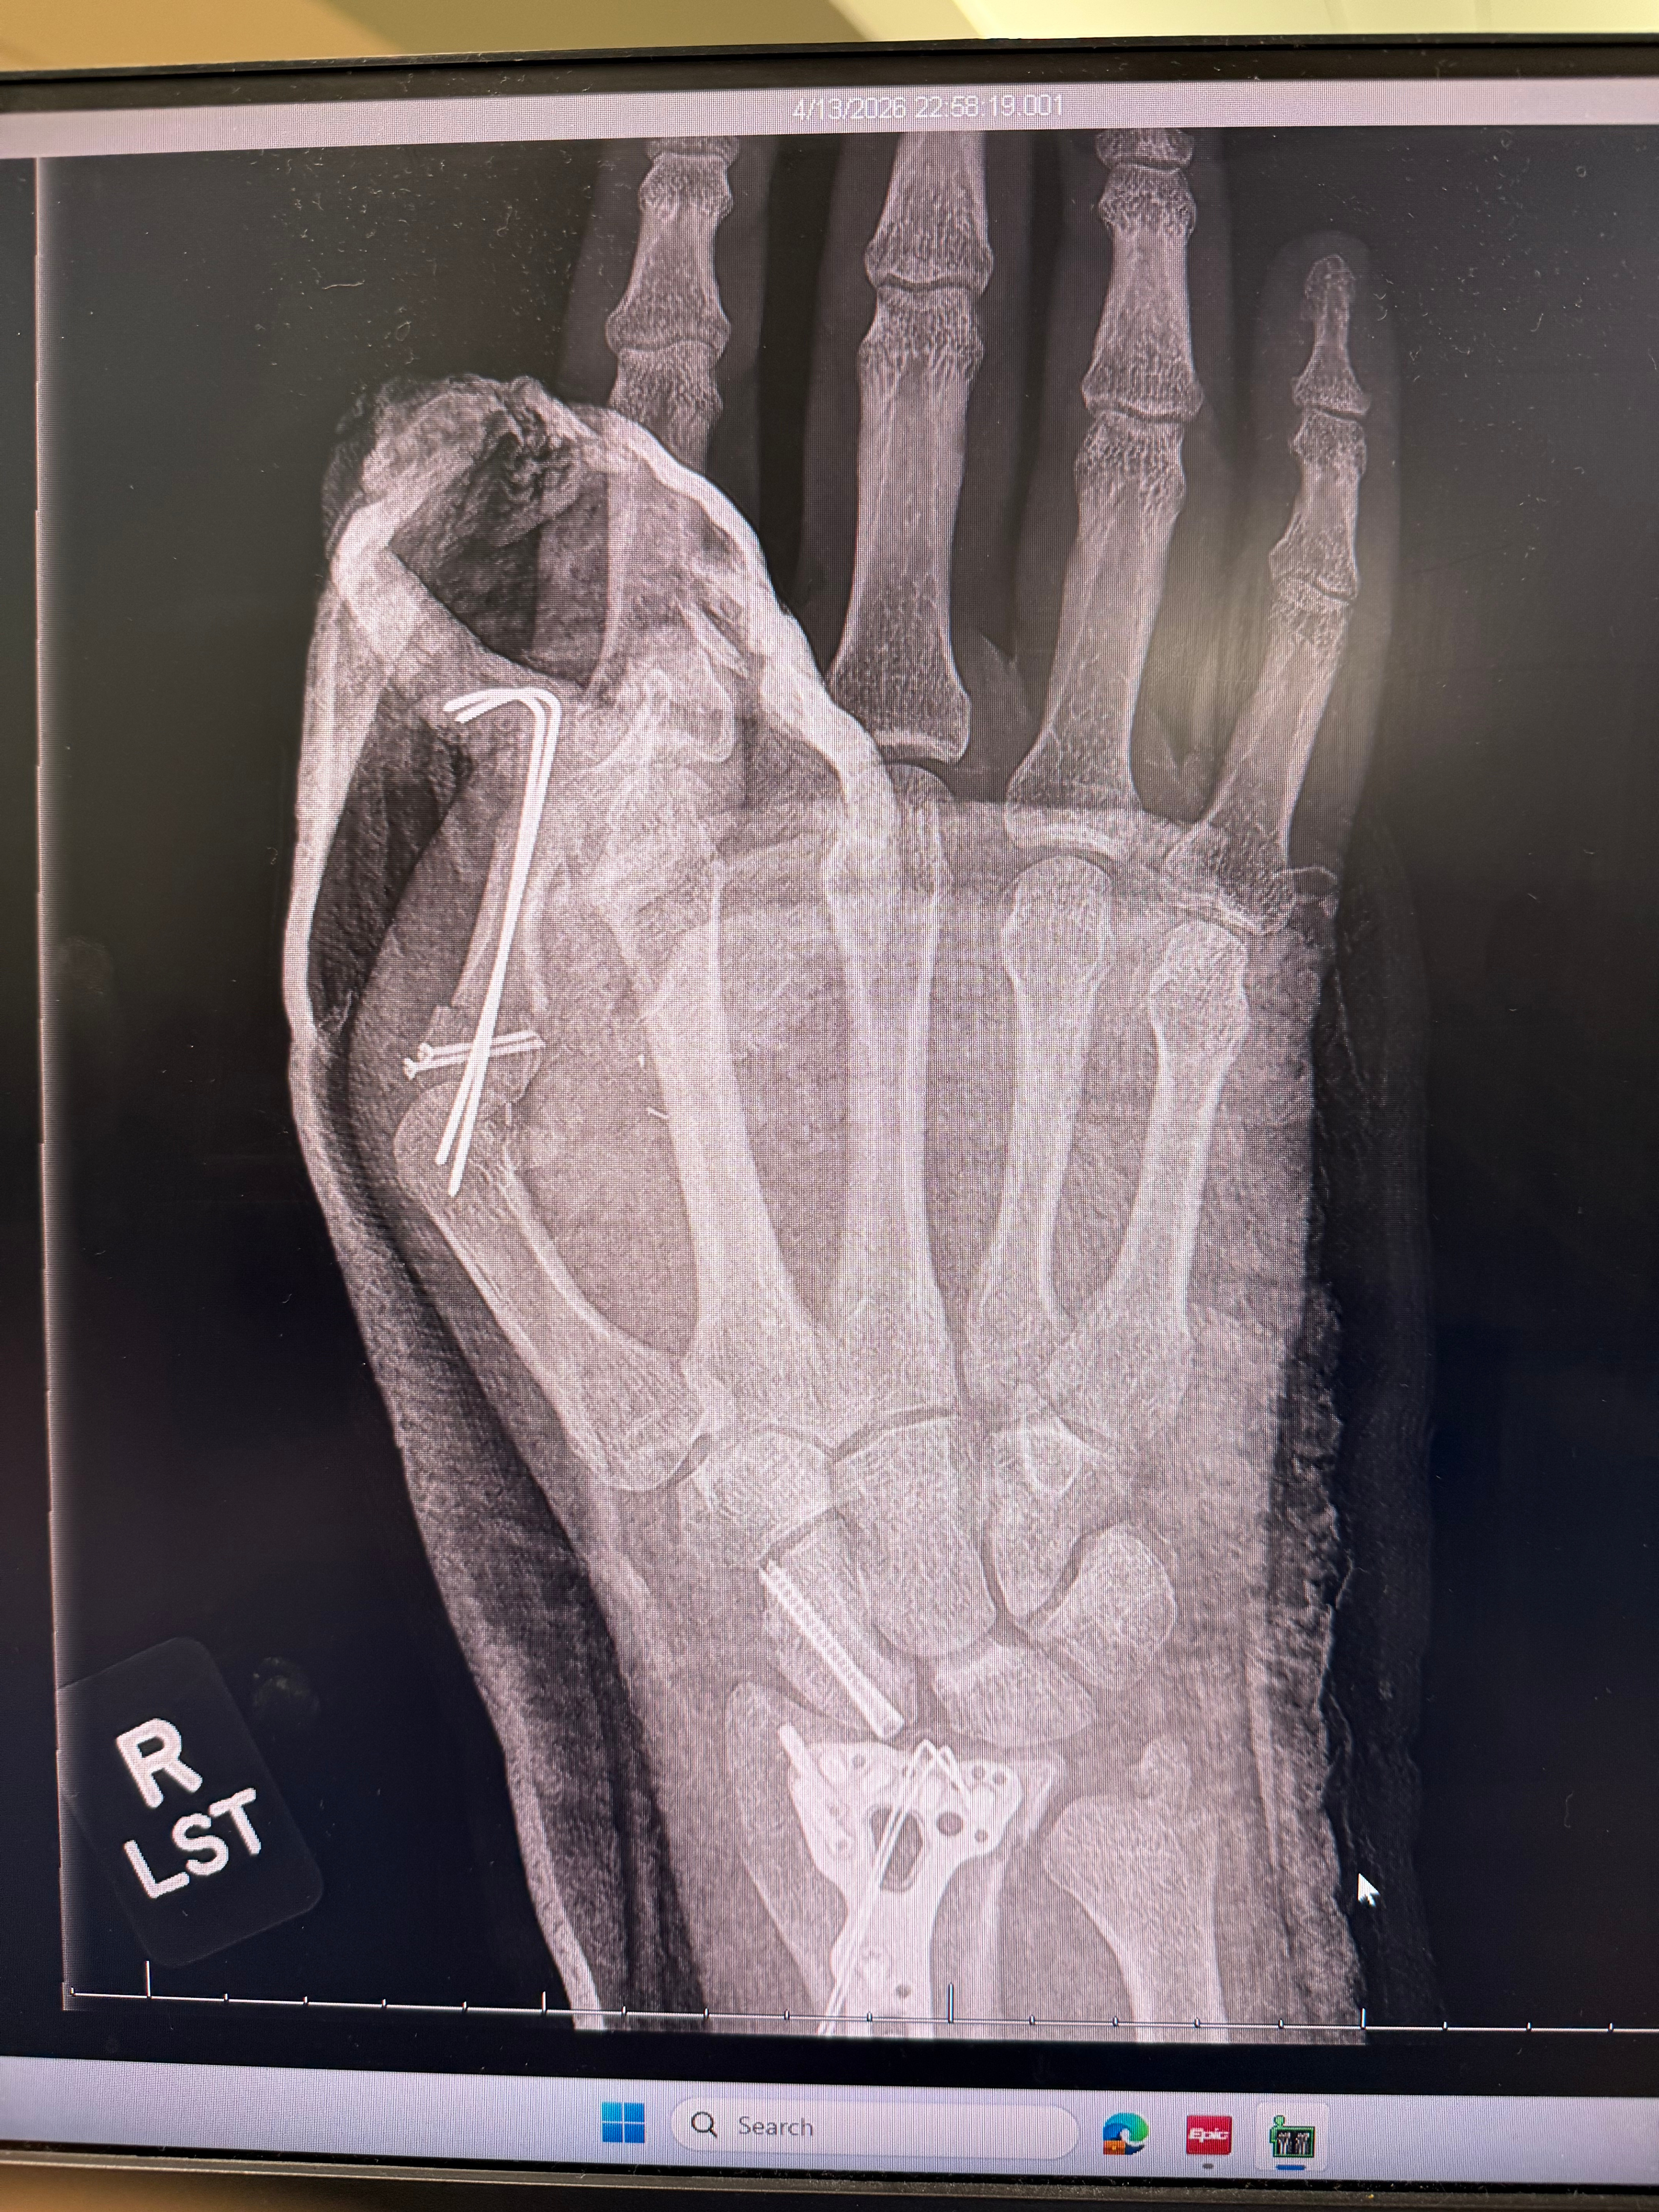

Another driver ran a red light, and I T-boned his car. The airbag deployed directly into my right hand, causing 10 fractures across my thumb, wrist, and arm, along with severed tendons and nerves.

At Stanford Medical Center, doctors told me my thumb was nearly torn off and might need to be amputated. I underwent an 8-hour reconstructive surgery (bone fixation, tendon repair, and nerve work), and thankfully, they were able to save my thumb. I now have hardware holding everything in place, but there is still significant uncertainty around long-term function and sensation. At the moment, much of my thumb, especially the part that grips, has no feeling.

As a musician and educator, everything I do depends on fine motor control and sensation in my hands. It’s still unclear how much I’ll regain. I likely won’t have answers for several months, after bone healing, a second surgery to remove hardware, and a long stretch of rehabilitation that could take up to a year.